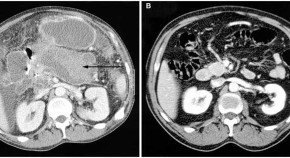

This article highlights two cases of massive lower gastrointestinal bleeding in patients on dialysis after rejection of kidney–pancreas transplants. One patient did not have the transplanted organ removed and eventually exsanguinated, while the second patient, whose rejected pancreas was removed, survived complications and did well. The cases illustrate that arterio-enteric bleeding should be included in the differential diagnosis of patients with rejected pancreatic transplants.